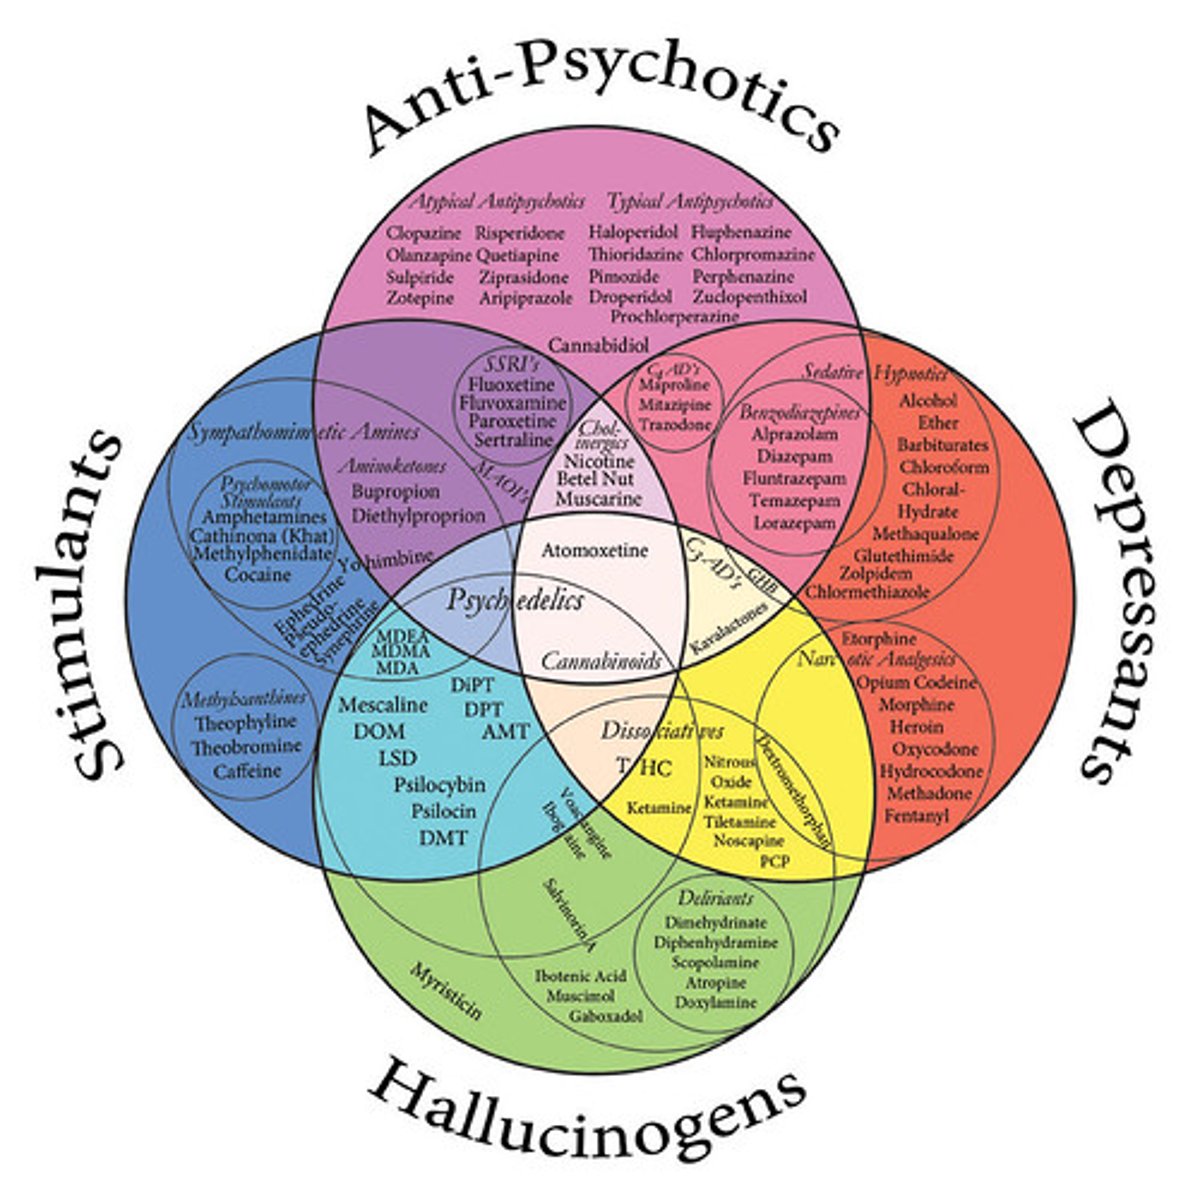

Psychoactive drugs

chemical substances that alter perception, mood, consciousness, perception, etc.

Stimulants

drugs that excite neural activity and speed up body functions

Depressants

drugs (such as alcohol, barbiturates, and opiates) that reduce neural activity and slow body functions

Hallucinogens

psychedelic drugs, such as LSD, that distort perceptions and evoke sensory images in the absence of sensory input